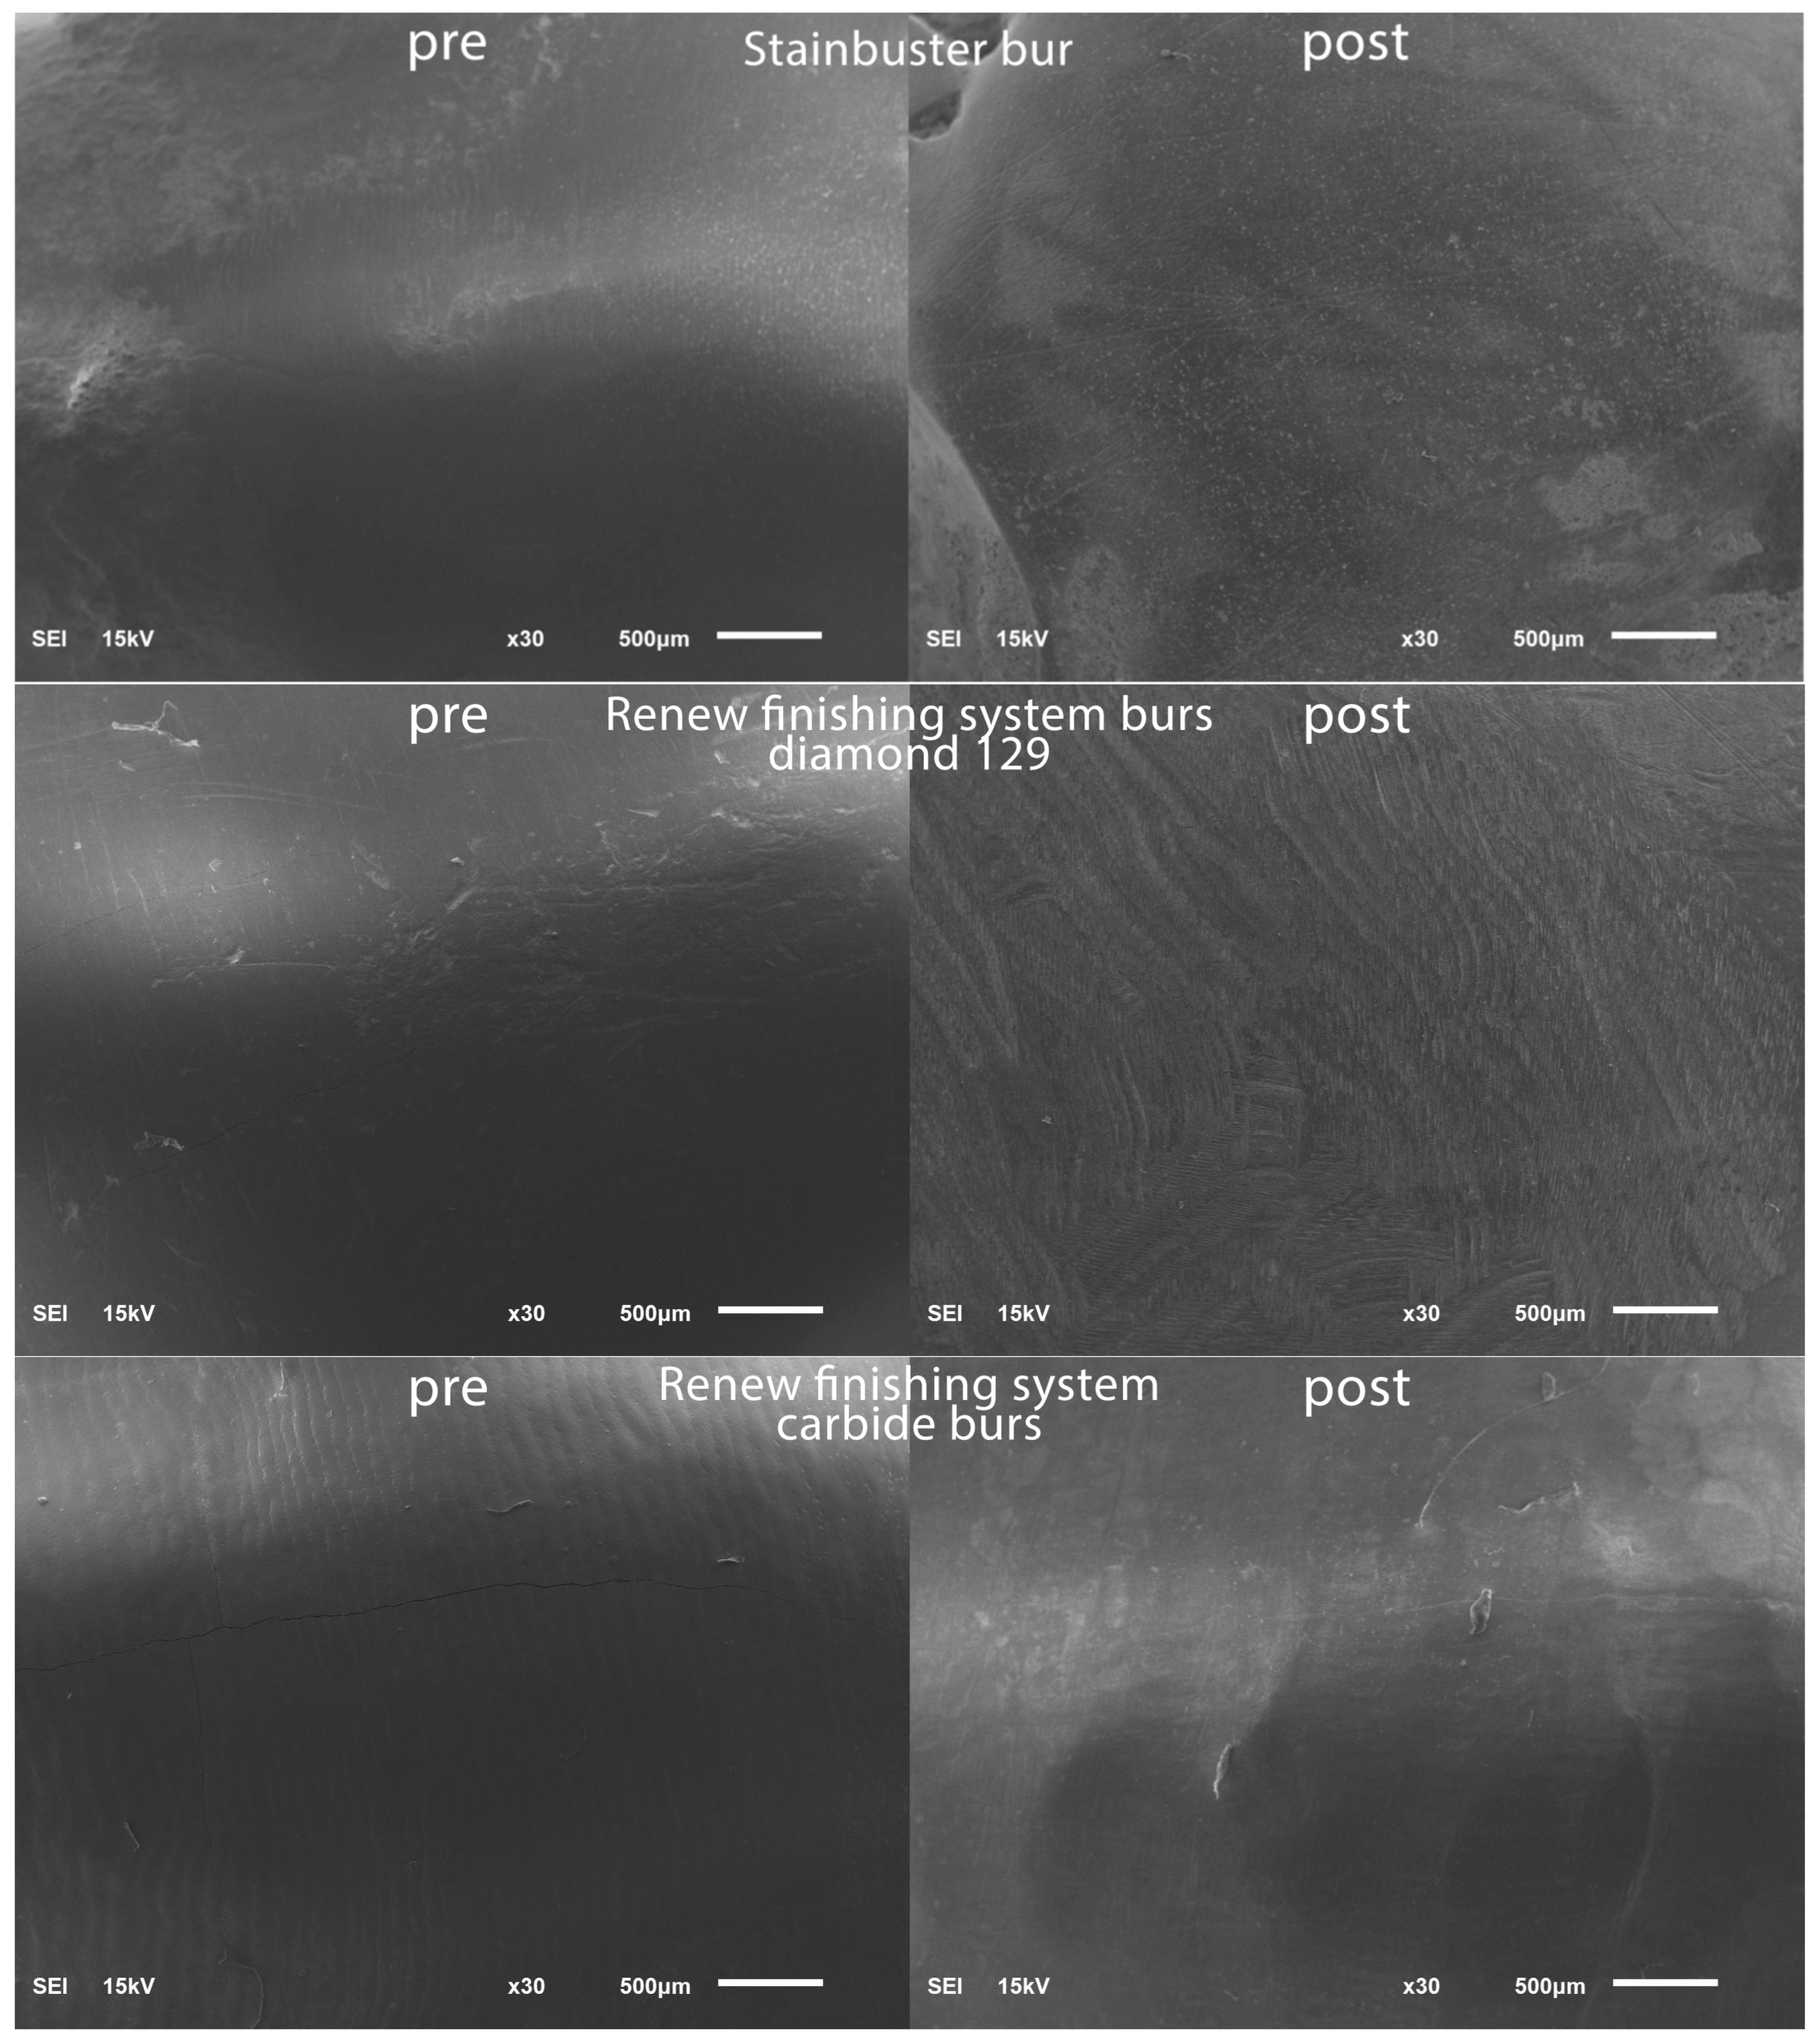

To establish a baseline for the surface roughness data, the teeth were positioned within a vinyl polysiloxane putty mold in preparation for scanning using a scanning electron microscope (SEM) (JSM 6610LV; Jeol, Tokyo, Japan). The SEM parameters employed included 15 kV voltage and a 10 mm working distance. To highlight specific regions of interest on the facial tooth surface, magnifications of 30× were chosen and representative SEM scans were captured in the pre-bracket bonding state; see Figure 1.

Figure 1.

SEM images pre-bracket bonding and post-bracket debonding.

Post-residual cement removal, enamel roughness measurements were performed in a similar routine to the pre-operative enamel surface roughness measurements and representative SEM scans were captured post-bracket debonding; see Figure 1.

Significant differences were noticed between the seven tested residual cement removal systems in terms of the surface roughness introduced into the enamel surface. The Sof-Lex system group demonstrated the smoothest post-finishing enamel surface. The Sof-Lex was found to significantly reduce surface roughness, as evidenced by the lowest enamel roughness measurements (2.335 μm), compared to the other tested methods. The Stainbuster system recorded the second lowest enamel roughness measurements (2.599 μm). The OneGloss system recorded the third lowest enamel roughness measurements (2.649 μm). Renew Finishing System Points recorded the fourth lowest enamel roughness measurements (3.299 μm). The Renew carbide bur system recorded the fifth lowest enamel roughness measurements (3.367 μm). The Enhance Finishing and PoGo Polishing system recorded the sixth lowest enamel roughness measurements (3.416 μm), whereas the Renew #129 diamond bur system was found to produce the highest levels of roughness on the enamel surface (4.716 μm), as evidenced by the surface profilometry and scanning electron microscopy (SEM) results. In related context, Bansal et al. [28] suggested that the Sof-Lex system ranked second after the Mylar matrix in terms of smoothing, while Shah et al. [24] reported that the Sof-Lex system also secured the second position, following the Enhance Finishing system.